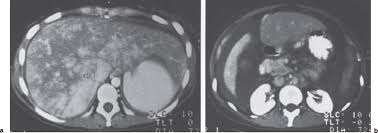

Chiasmata -mə-tə or chiasmas also chiasms 1. Esophageal varices are extremely dilated sub-mucosal veins in the lower third of the esophagus. Located in metro Denver northern Colorado and western Nebraska serving all of the Front Range our team consists of board-certified and fellowship-trained interventional radiologists. This results in hepatic congestion similar to Budd-Chiari syndrome and post-sinusoidal portal hypertension. The patients condition should be monitored throughout the procedure. They are most often a consequence of portal hypertension commonly due to cirrhosis. Toxic injury to liver sinusoids causes sloughing of endothelial cells that embolize to hepatic venules and cause eventual fibrosis of the venules. Coin in the Esophagus. There is no clear consensus regarding the number of occluded veins some authors claim that there should be at least one occluded hepatic vein 7 others state that there are no significant.

Carcinoma of the Colon. Budd-Chiari syndrome a blockage in one or more veins that carry blood from the liver back to the heart. And coumarin skin necrosis adrenal gland hemorrhage and infarction. Toxic injury to liver sinusoids causes sloughing of endothelial cells that embolize to hepatic venules and cause eventual fibrosis of the venules. Chiari malformation CM is a structural defect in the cerebellum characterized by a downward displacement of one or both cerebellar tonsils through the foramen magnum the opening at the base of the skull. Embolism and thrombosis of. La présence dune ou plusieurs affections prothrombotiques est fréquente La prise en charge repose sur un traitement anticoagulant précoce le traitement de l.